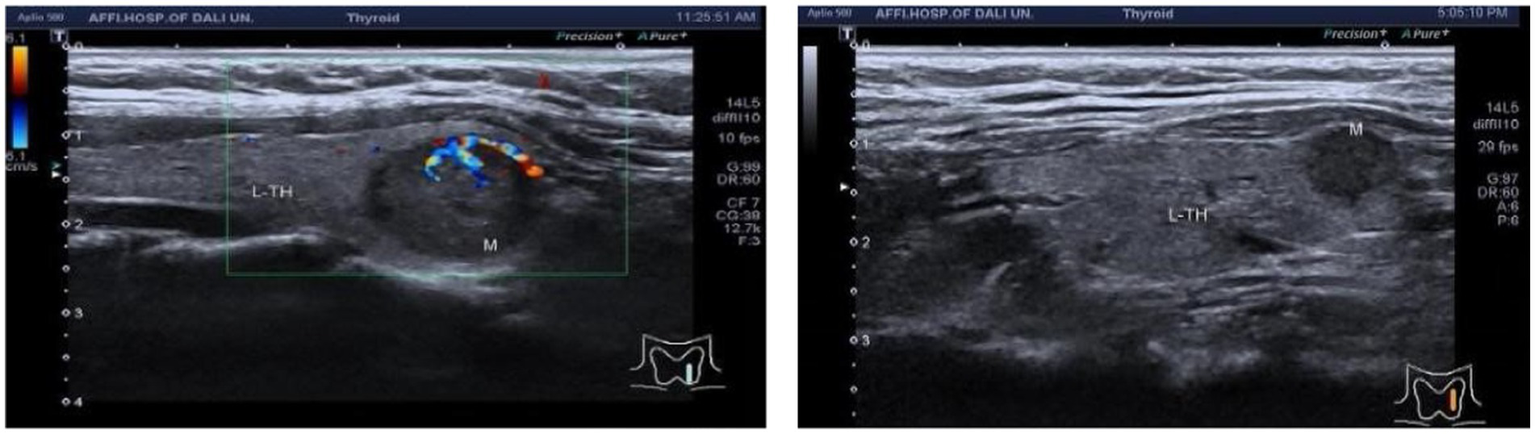

The correlation between ultrasonic characteristics of C-TIRADS and anxiety states needs to be further investigated

In a cohort of 303 patients, the HAMA results indicated that 126 patients exhibited normal anxiety levels, while 177 patients showed abnormal anxiety levels. Specifically, the HAMA results were categorized as follows: 126 patients without anxiety symptoms, 97 with possible anxiety, 47 with definite anxiety, 22 with definite and obvious anxiety, and 11 with possible severe anxiety. An ordinal logistic regression analysis was conducted to assess the impact of anxiety factors on c-tirads classification. These findings suggest that the presence of an unsmooth edge of TN is a risk factor for anxiety in patients, whereas protrusion outside the capsule is an influencing factor [p = 0.037, 0.028; B = 5.892, −5.723; OR, 95% CI: 362.080 (1.408–93142.282), 0.003 (0–0.054), Figures 4–7].

Figure 4

Ultrasound image of nodular lesion in the left lobe of the thyroid gland, C-TIRADS classification: 4A.

Figure 6

Ultrasound image of nodular lesion in the left lobe of the thyroid gland, C-TIRADS classification: 4B class, TN edge smooth, ultrasound image of nodular lesion in the right lobe of the thyroid gland, C-TIRADS classification: 4C class, TN edge not smooth.